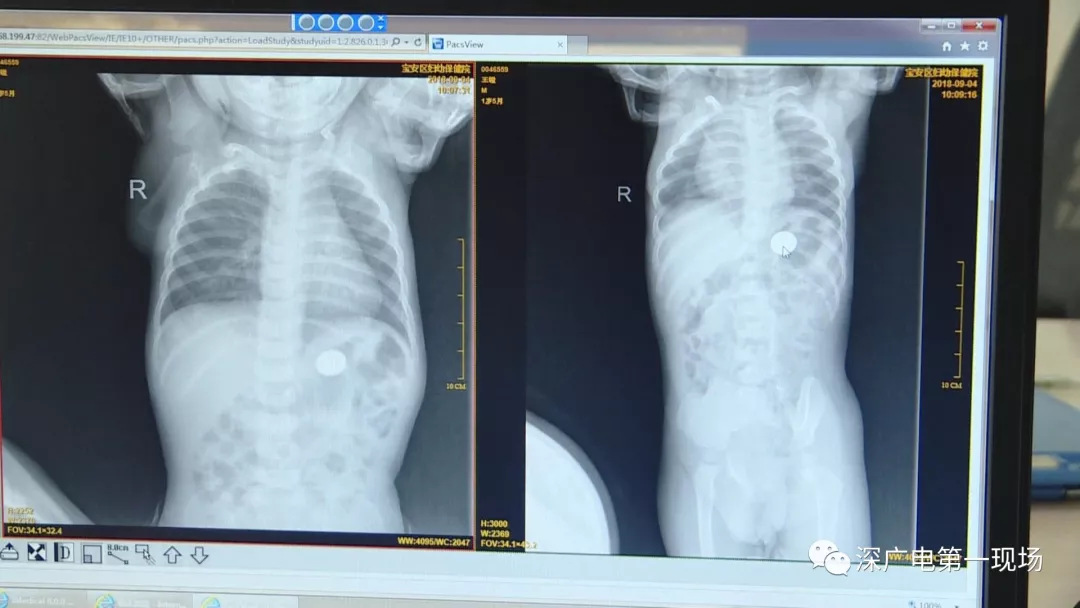

因禍得福!1歲男童摔傷送院 醫(yī)生竟從胸片中發(fā)現(xiàn)了這個(gè)…